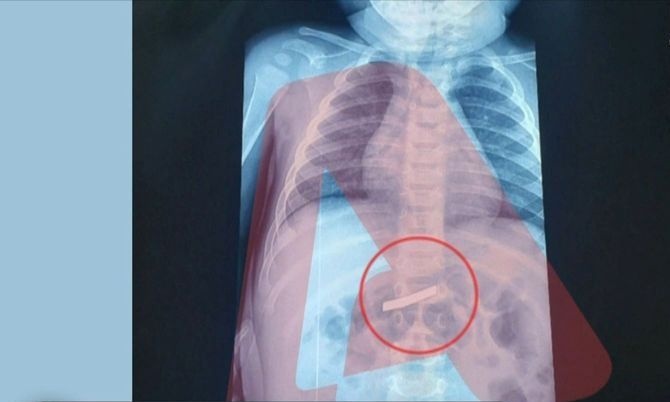

Αίσια έκβαση είχε η περιπέτεια για το τρίχρονο παιδί που κατάπιε ξυραφάκι και μεταφέρθηκε επειγόντως στο νοσοκομείο, όπου υπεβλήθη εσπευσμένα σε χειρουργική επέμβαση για να αφαιρεθεί το επικίνδυνο αντικείμενο.

Το χειρουργείο ήταν πετυχημένο και το μικρό παιδί αναρρώνει πλέον στο σπίτι, καθώς δεν χρειάστηκε να νοσηλευτεί.

Όμως τα περιστατικά είναι αρκετά, όπως διαπιστώνει το ρεπορτάζ του καναλιού, καθώς στα παιδιατρικά των νοσοκομείων δεν είναι λίγες οι περιπτώσεις μικρών παιδιών που καταφθάνουν με κάτι...στο στόμα. Όπως ένα 4χρονο αγοράκι πριν από λίγες ημέρες που κατάπιε μία παραμάνα και μεταφέρθηκε αμέσως στο Παίδων Αγλαΐα Κυριακού.